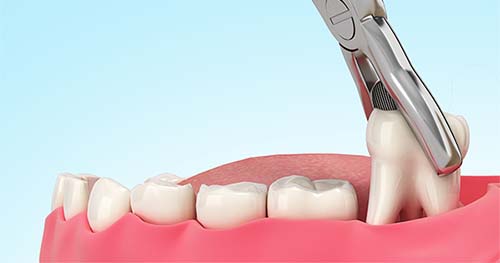

Para el cuidado después de una extracción dental, debes aplicar hielo, comer dieta blanda y fría, no fumar ni enjuagarte la boca enérgicamente durante las primeras 24 horas, y mantener una buena higiene a partir del día siguiente. También es fundamental tomar analgésicos según sea necesario, descansar, dormir con la cabeza elevada y seguir las instrucciones específicas de tu dentista.